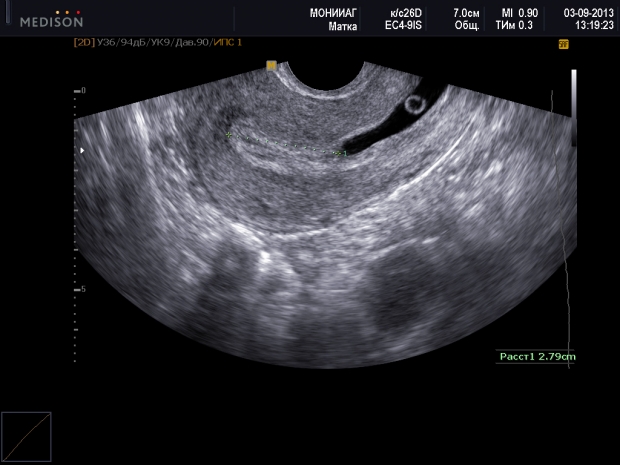

Внематочная беременность: фото УЗИ

Далее проводится влагалищное обследование и ультразвуковая диагностика. УЗИ является очень информативным методом при внематочной беременности, так как позволяет отличить ее от других заболеваний с похожими симптомами. Наиболее надежным признаком эктопической беременности считается обнаружение плодного яйца с развивающимся эмбрионом за пределами матки. При этом фиксируется сердцебиение эмбриона, а если беременность достигла 7 недель, можно заметить и его движения. Однако такая ситуация наблюдается не более чем в 8% случаев.